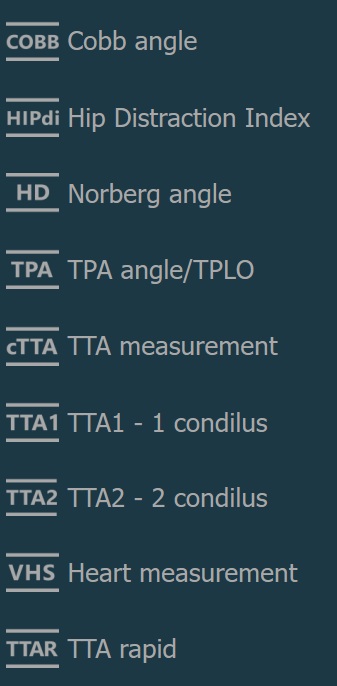

Advanced Measurements¶

Cobb angle

Hip Distraction Index

Norberg angle

TPA angle/TPLO

TTA measurement

TTA1 - 1 condilus

TTA2 - 2 condilus

Heart measurement

TTA rapid